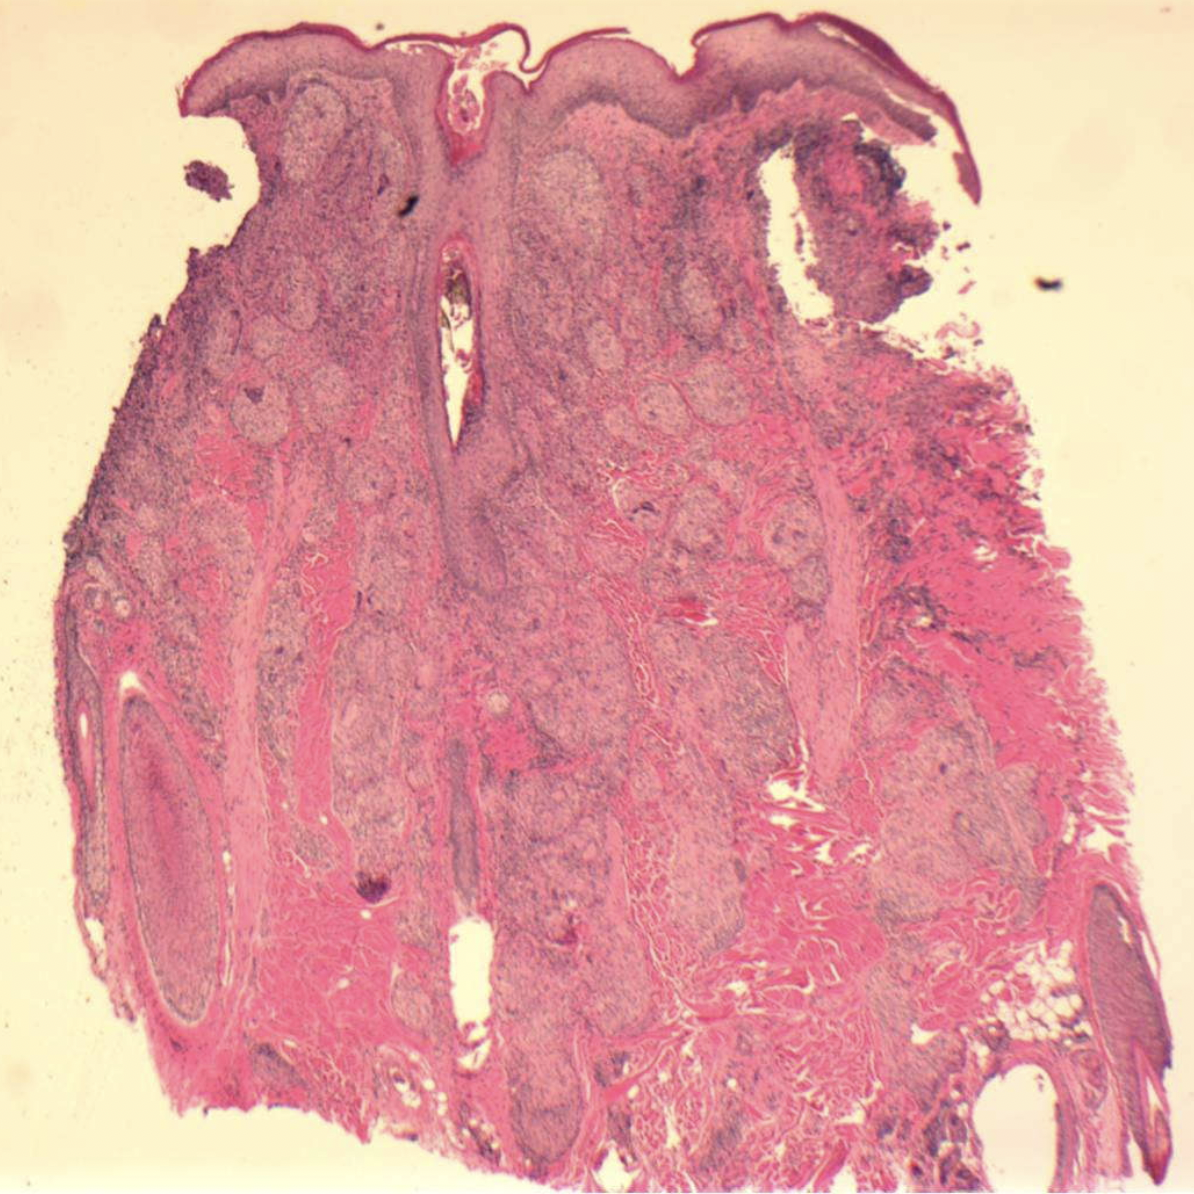

Biopsies of scalp sarcoid will show the classic pattern of inflammation that characterizes this disease: sarcoidal granulomas in the dermis. The key to the diagnosis is the characteristic noncaseating epitheloid granulomas. The central area has lymphocytes, macrophages, multinucleate giant cells and the is all surrounded by CD8 and CD4 positive T cells (and fibrosis).

Skin Biopsy (4 mm punch) showing Sarcoidosis. Biopsy from the vertex scalp showed a dense dermal granulomatous infiltrate of lymphocytes, histiocytes, multinucleated histiocytes, and scattered neutrophils with few terminal hairs. There was significant dermal atrophy. Image from Long T et al. Severe scalp sarcoidosis in an unlikely patient. JAAD Case Rep . 2020 Apr 24;6(11):1165-1166. Image used here with creative commons license.

Histopathology from a 43 year old patient with scalp sarcoidosis. The image shows typical ‘naked’ epithelioid granulomas with Langans type giant cells. There are no adnexal structures here suggesting this is a scarring alopecia. Image from Ghosh A et al. Single lesion of sarcoidosis presenting as cicatricial alopecia: a rare report from India. Int J Trichology . 2014 Apr;6(2):63-6. Image used with creative commons license.